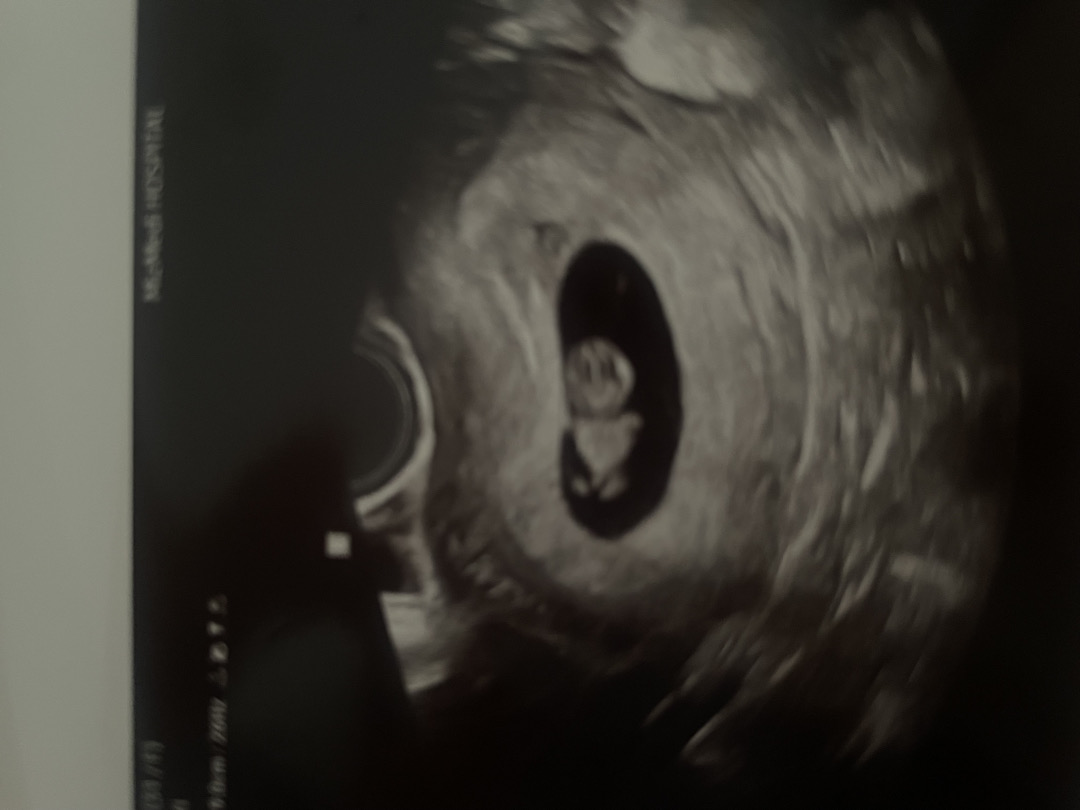

8주6일 초음파 머리

오늘 손발 처음 확인했는데 다른 분들 초음파들이랑 봤는데 몸보다 머리가 엄청 큰거같아요....한번봐주세용😭😭